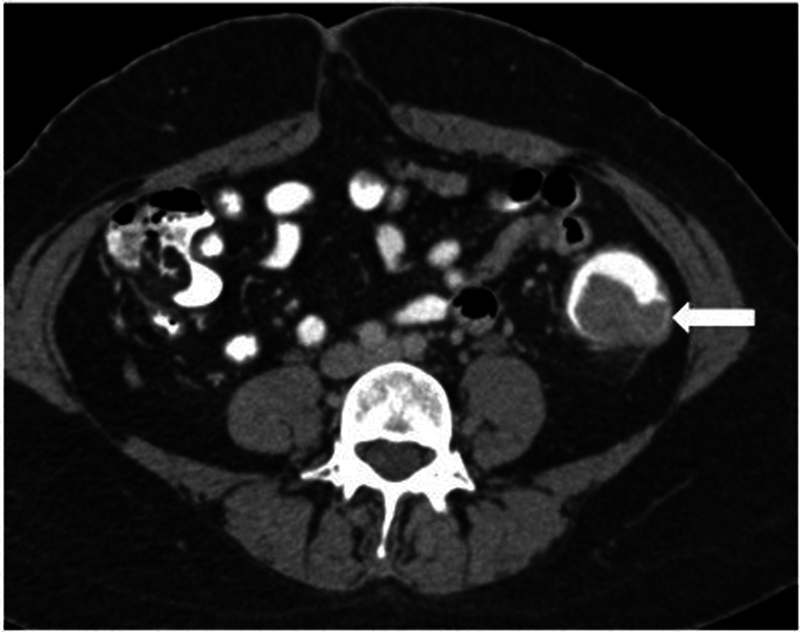

本文综述了计算机断层扫描(CT)、CT结肠镜检查(CTC)和磁共振成像(MRI)在结直肠癌的诊断、分期、疗效评估和随访中的作用。对于CT扫描,需要事先进行肠道准备。这是通过使用口服或直肠造影剂来增强结肠成像。像空气或二氧化碳之类的阴性对比有助于通过扩张结肠来检测息肉和肿块。虚拟结肠镜检查为息肉和癌症的检测提供了一种低辐射的选择。动脉和静脉相CT图像的静脉造影剂管理对于已知结肠癌病例的完全分期和残留/复发疾病的评估也很重要。对于MRI来说,多平面的高分辨率t2加权图像很重要,弥散加权成像(DWI)序列对重新定位很重要。一般不推荐静脉造影剂。对比增强CT和MRI用于淋巴结和远处转移分期,特别注意盆腔侧壁淋巴结。如果发现不明确或怀疑复发,应考虑进行正电子发射断层扫描(PET) CT进一步评估。

The present review highlights the role of computed tomography (CT), CT colonography (CTC), and magnetic resonance imaging (MRI) in the diagnosis, staging, response evaluation, and follow-up of colorectal cancer. For a CT scan, prior bowel preparation is required. This is done to enhance imaging of the colon with the use of oral or rectal contrast agents. Negative contrast like air or carbon dioxide are helpful in detecting polyps and masses by distending the colon. Virtual colonoscopy offers a lower-radiation alternative for polyp and cancer detection. Intravenous contrast administration with arterial and venous phase CT images is also important in complete staging of a known case of colon cancer and for evaluation of residual/recurrent disease. With respect to MRI, high-resolution T2-weighted images in multiple planes are important, with diffusion-weighted imaging (DWI) sequences being important for restaging. Intravenous contrast is not generally recommended. Contrast-enhanced CT and MRI are used for nodal and distant metastasis staging, with special attention to the pelvic side wall nodes. Positron emission tomography (PET) CT is to be considered for further evaluation if the findings are unclear and recurrence is suspected.